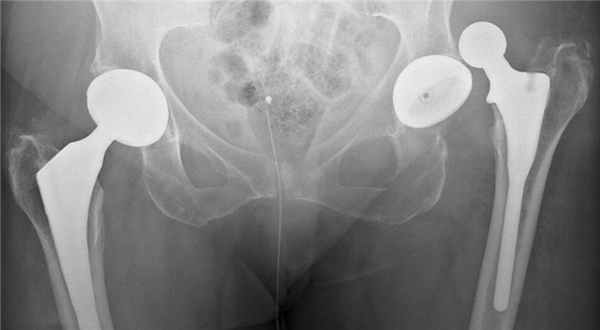

В случаях, когда тазобедренный сустав утрачивает свои функции (стирается гладкий хрящ, который обеспечивает легкоескольжение головки бедра в вертлужной впадине) и любые движения вызывают нестерпимую боль, пациентам проводят операцию эндопротезирования. Эндопротез – это искусственный заменитель какого-либо органа человека (выполняющий его функцию), который располагается внутри тела человека. Эндопротезирование тазобедренного сустава – это операция по замене пораженных компонентов сустава на эндопротез, который обладает анатомической формой здорового сустава и дает возможность осуществлять полный объём движений. Вывихи поле такой операции происходят весьма редко, но случаются, и в основном это вывихи головки эндопротеза.

Вывих протеза тазобедренного сустава

После тотального эндопротезирования тазобедренного сустава, он подвергается вывиху без травмы у почти 2% пациентов. Чаще вывих происходит назад.

Часто эффективно закрытое вправление, особенно при впервые возникшем вывихе, но иногда требуется оперативная ревизия тазобедренного сустава.